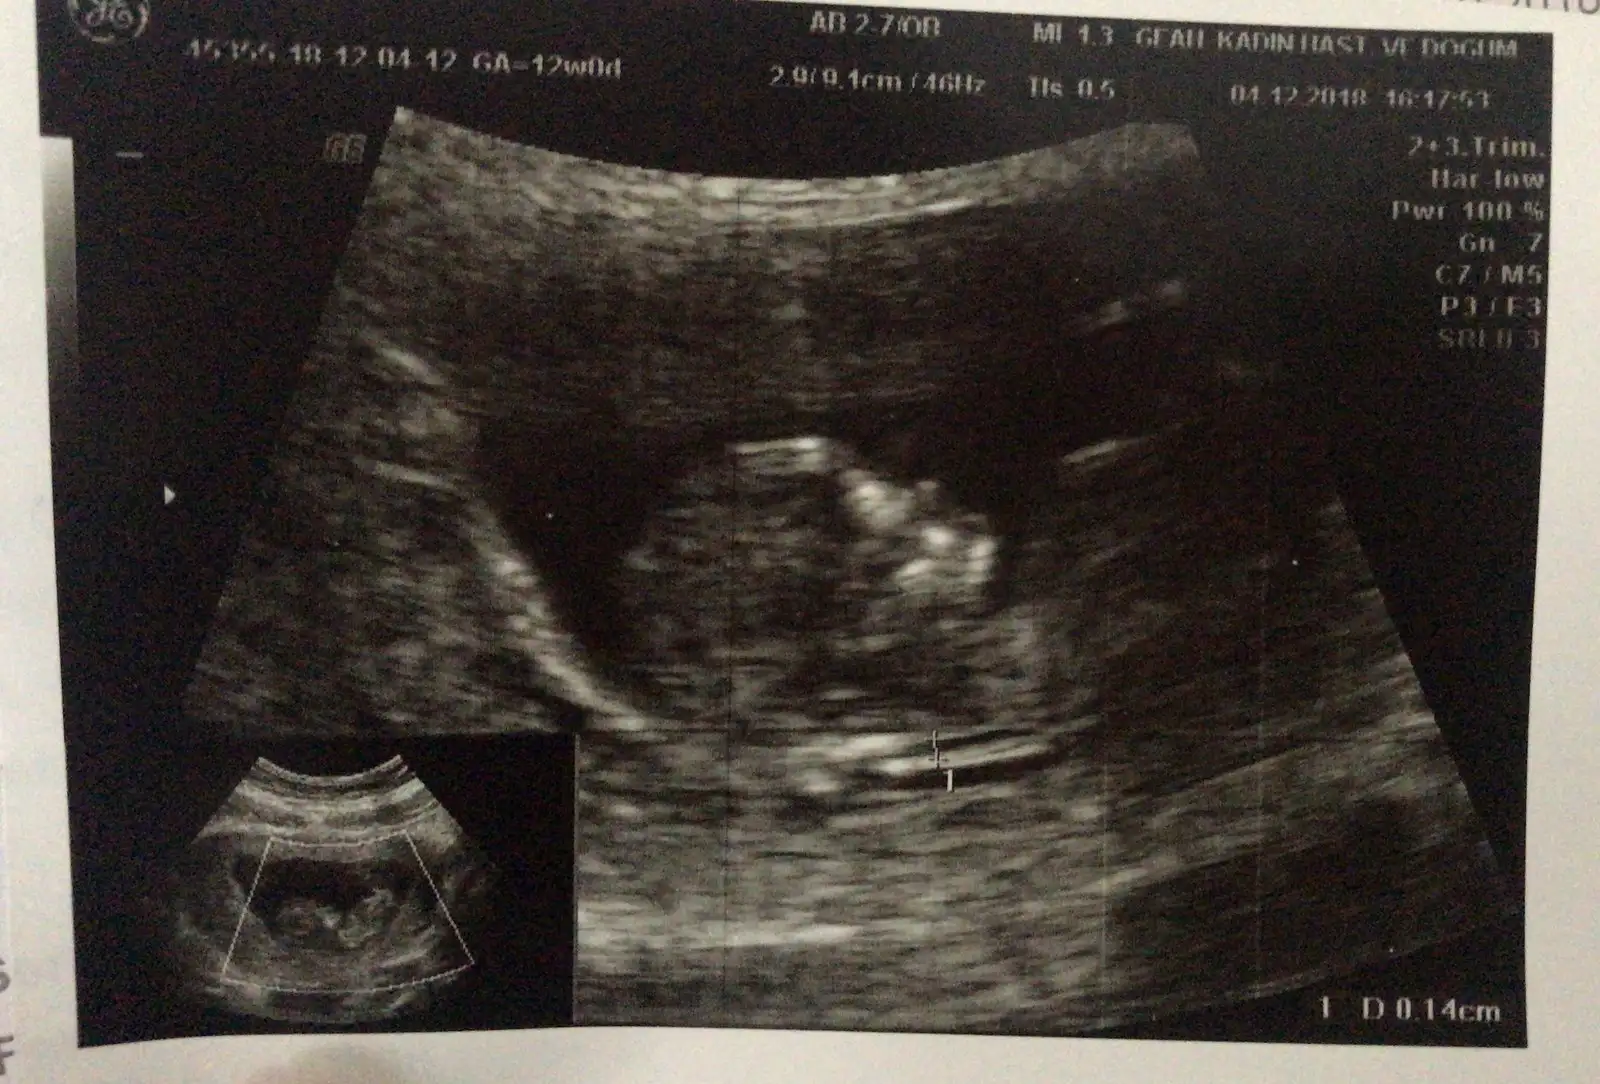

Ya canım sen bilirsin ama sorma bence çünkü cidden erken bana 11+4 te kızı andırıyor denildi 12+5 te erkek cıkıntısı var denildi yani sorduğuma pişman oldum :) 14+5te gitcem sorsam mı bilemedimyarın devlete gidicem 11+2 çıktı bugün ikili test sırasında sorsam cinsiyet tahmini yapar mı acaba. veya uzun mu sürüyor muayenesi ben az biraz anlıyorum ultrasondan ayrıntılı incelerse ssormama bile gerek kalmaz diye düşünüyorum

Ben dün gittim ikili yapacakti ama küçük su an dedi , haftaya Çarşamba gideceğim tekrar . Detaylı organ incelemesi yapacaklar . Umarım sana da erken demezler.yarın devlete gidicem 11+2 çıktı bugün ikili test sırasında sorsam cinsiyet tahmini yapar mı acaba. veya uzun mu sürüyor muayenesi ben az biraz anlıyorum ultrasondan ayrıntılı incelerse ssormama bile gerek kalmaz diye düşünüyorum